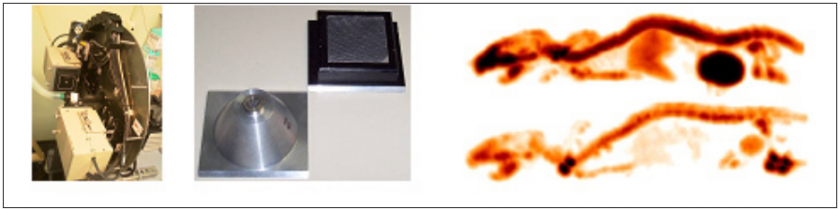

Diseño y desarrollo de un sistema micro-CT de alto rendimiento para pequeños animales de laboratorio

Se describe la implementación de un escáner micro-CT adecuado para ser utilizado como elemento complementario en

diferentes escáneres PET para pequeños animales. El diseño básico del sistema se basa en el montaje de un tubo micro-foco de rayos-X y un detector digital plano sobre un soporte rotatorio.

We have developed an X-ray cone beam tomograph for in vivo small-animal imaging using a flat panel detector (CMOS technology with a columnar CsI scintillator plate) and a microfocus X-ray source in a geometric configuration with 1.6 magnification and 7.5 cm2 field of view. This work presents an initial characterization of this new system. We measured the detector modulation transfer function (MTF), detector stability, system resolution, the quality of the reconstructed tomographic images and radiated dose.

| JOURNAL | IEEE Nuclear Science Symposium Conference Record, 2006 |

The goal of this work was the development of a low-cost micro-CT scanner, which could be used as an add-on in our previously developed PET systems for small-animals. The scanner design consists of a single-processor computer controlling a micro-focus X-ray tube and a flat panel detector, assembled in a common rotating gantry. The geometrical configuration was selected to achieve a spatial resolution of about 12 lp/mm with a field of view appropriate for small animals such as mice and rats. The radiated dose is controlled during the acquisition by two different elements: an aluminium filter and a tungsten shutter, attached to the X-ray source. The shutter is controlled by the computer in synchronism with the gantry rotation and the detector image integration.